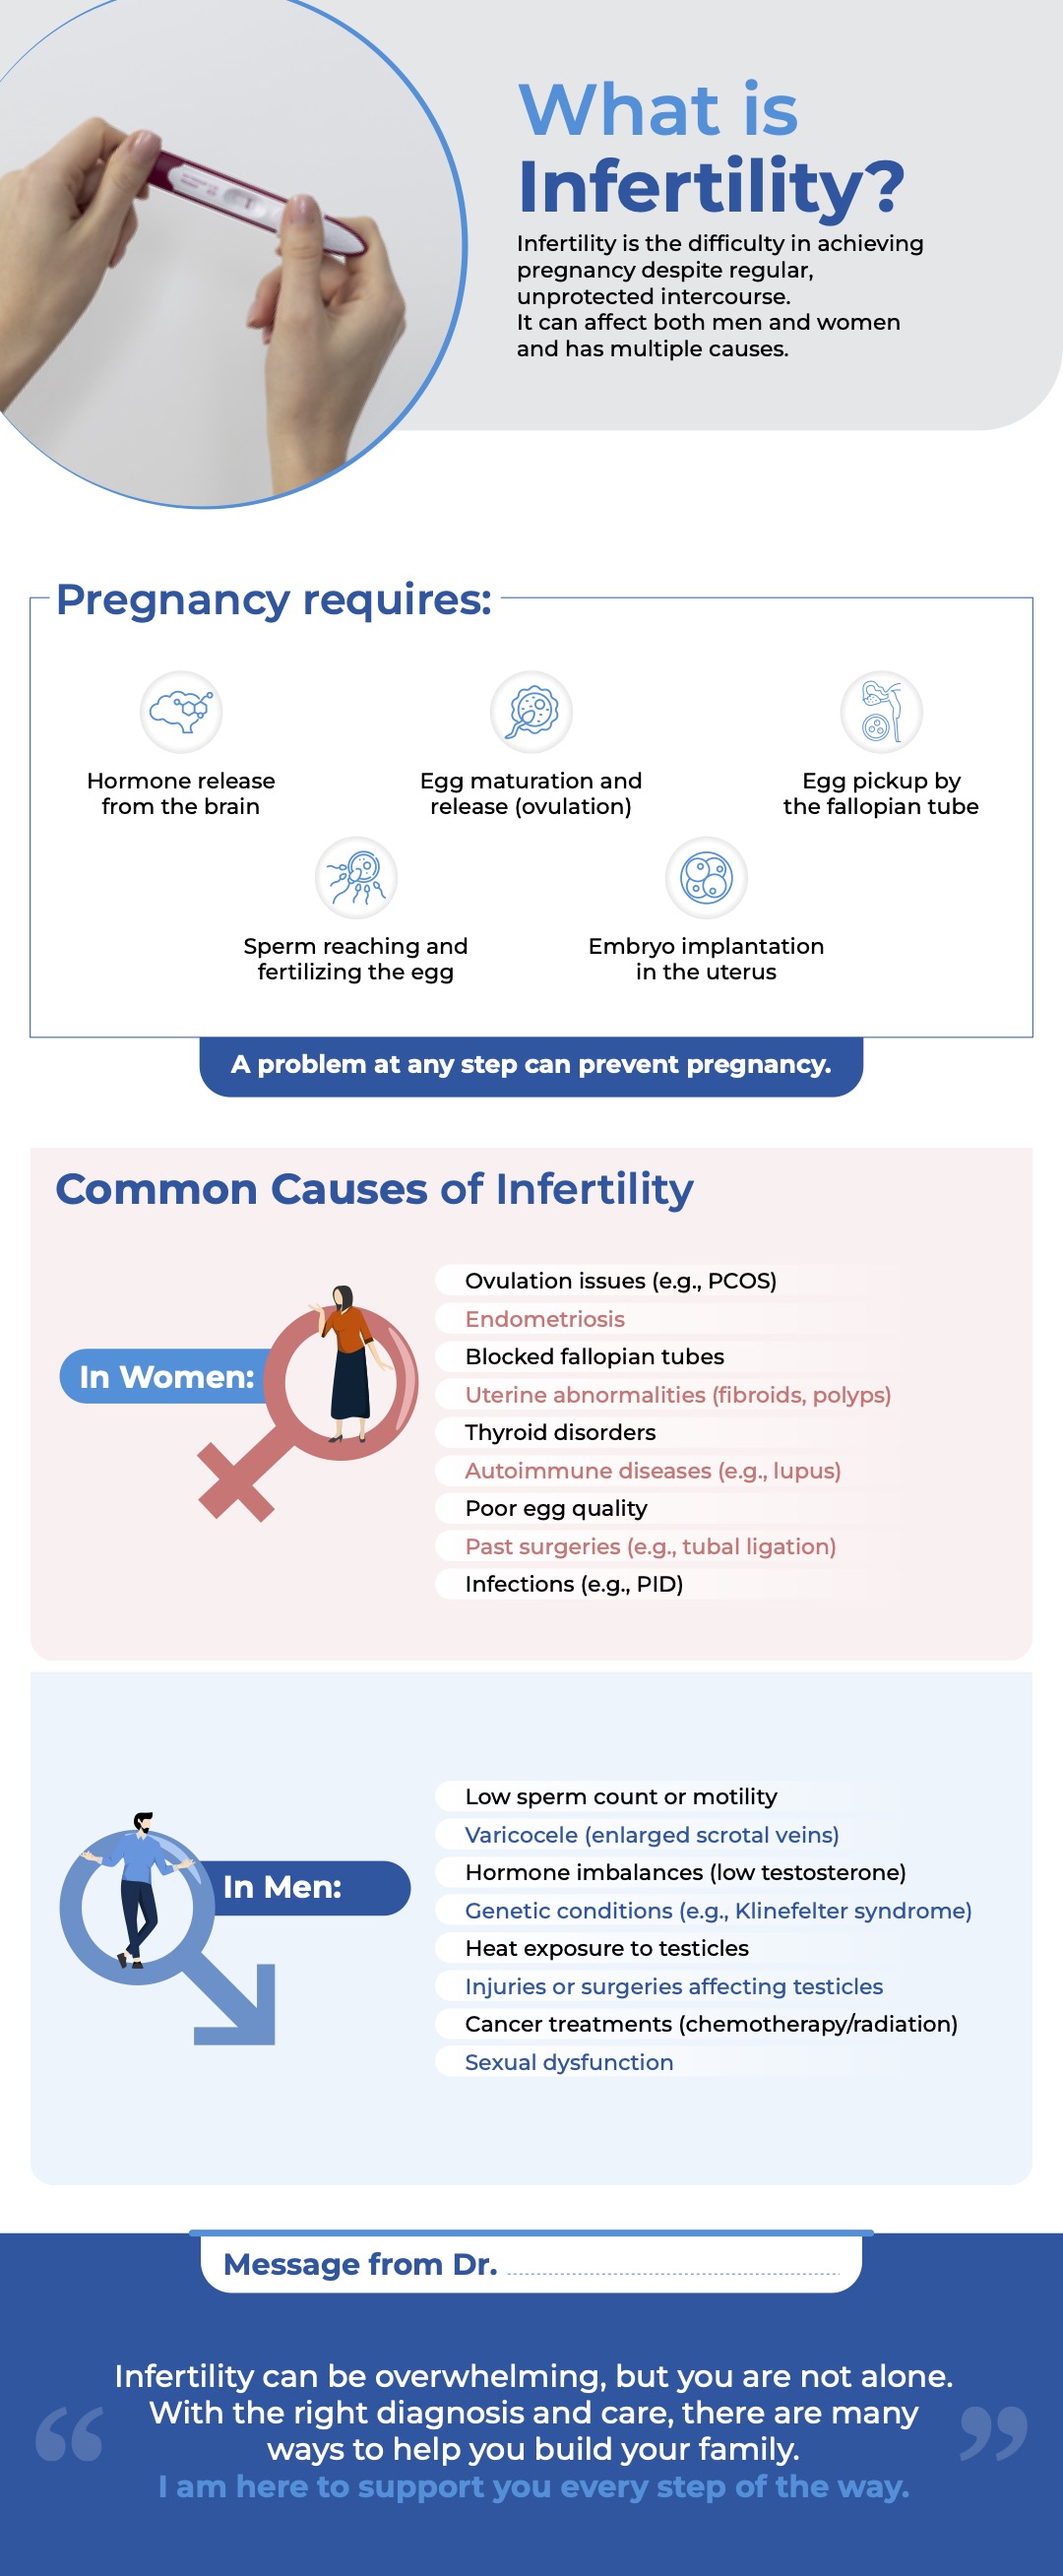

Infertility

Causes of Infertility in woman: Ovulation disorders, Blocked or damaged fallopian tubes, Endometriosis, Uterine or cervical abnormalities,Age-related decline in fertility and in men: Low sperm count or poor sperm motility, Hormonal imbalances, Varicocele, Genetic conditions, Lifestyle factors etc.

Infertility evaluation typically involves a thorough medical history, physical exams, and diagnostic tests such as hormone evaluations, ultrasound imaging, semen analysis, and in some cases, advanced procedures like hysterosalpingography (HSG) or laparoscopy.

What is Infertility?